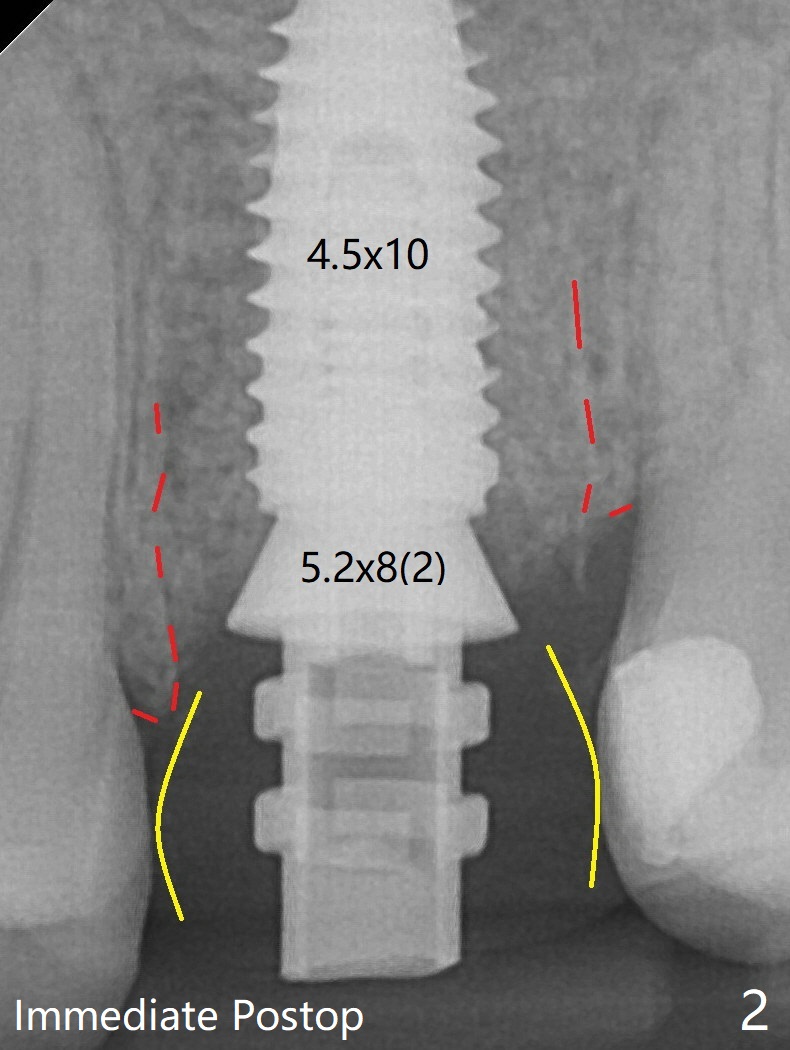

Advantage is that an immediate provisional (Fig.2 yellow lines; Fig.3 P) has an ideal emergency profile so that there is less chance of food impaction associated with the future permanent crown. Red dashed line: mesial and distal crests. Bone graft appears to be integrated to the native bone and the implant 14 months postop (Fig.5).32岁女左上6即刻种植(图2:4.5x10毫米),内提升,使用临时基台(5.2x8(2)毫米)即刻修复,有可能建立理想emergency profile (黄线,即临时牙冠),红虚线代表近中,远中牙槽嵴,后者与植体/基台之间是骨粉。术后14个月,植体螺纹没有暴露,骨粉好像与植体和牙槽嵴整合了(图5),放置修复基台。